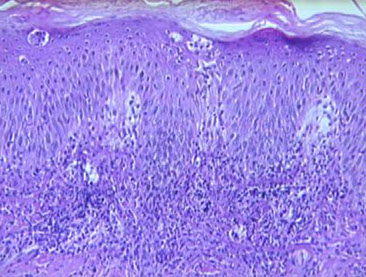

Hailey-Hailey disease

Micro: "dilapidated brick wall" appearance of acantholysis

- also see acanthosis

- pinkish halo surrounds nuclei

AD inherited dz (ATP2C1 gene [for a Ca2+ pump]) c poor cellular adhesion; a genodermatosis (??)

- "wet tissue paper" look of affected skin in neck and intertriginous areas; not as diffuse as Hailey-variant of Grover's disease

- Not an ab-mediated dz (negative IF)

- acantholysis should NOT involve the hair follicle (if it does, then the dx is probably pemphigus vulgaris)